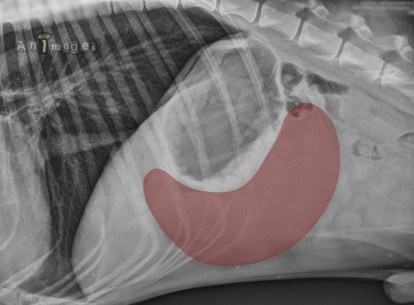

La majorité d’entres vous aviez vu juste. La rate était plus grosse et bel et bien déplacée de façon anormale, occupant le côté droit de l’abdomen et glissant sous l’arche costale pour repousser et déformer l’estomac. Sur la latérale, elle prend la forme d’un « C » inversé, une signature assez caractéristique de torsion splénique. Ce signe n’est pas toujours évident cependant, surtout lorsque de l’épanchement péritonéal s’accumule et réduit le détail péritonéal.

Afin de confirmer cette suspicion et d’écarter d’autres possibilités de splénomégalie, une échographie a été réalisée. Les premières images ont confirmé le localisation anormale de la rate qui s’incurve sous l’arche costale pour ensuite suivre la paroi abdominale droite. Cette rate est augmentée de volume et diffusément hétérogène. Les veines spléniques sont orientées vers la gauche au lieu de l’inverse et disparaissaient dans des gras hyperéchogènes sans pouvoir suivre leur connexion avec la veine splénique primaire.